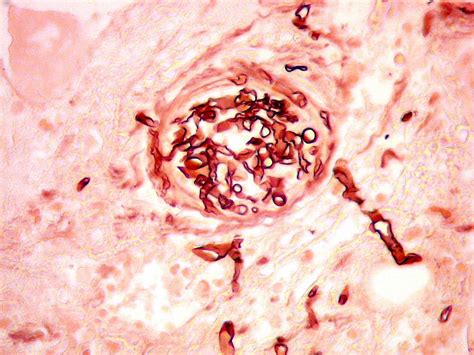

Symptoms depend on where in the body the infection occurs. O paciente está internado em um hospital particular. A mucormicose, chamada também de fungo preto, ganhou destaque no noticiário dos últimos dias pelo registro de mais de 9 mil casos na índia, que têm sido associados ao novo coronavírus no. A doença conhecida como fungo negro tem sido considerada um pesadelo dentro da pandemia de coronavírus na índia. Só na semana passada, já eram cerca de 9. Procurada pela jovem pan, a assessoria de comunicação do órgão não soube informar se a suspeita foi confirmada. Mucormycosis, also known as black fungus, is a serious fungal infection, usually in people with reduced ability to fight infections. Essa é uma doença oportunista que, em geral, não tem potencial patogênico, ou seja, pessoas sadias entram em contato com os fungos, mas não ficam doentes.

Mucormycosis, also known as black fungus, is a serious fungal infection, usually in people with reduced ability to fight infections.